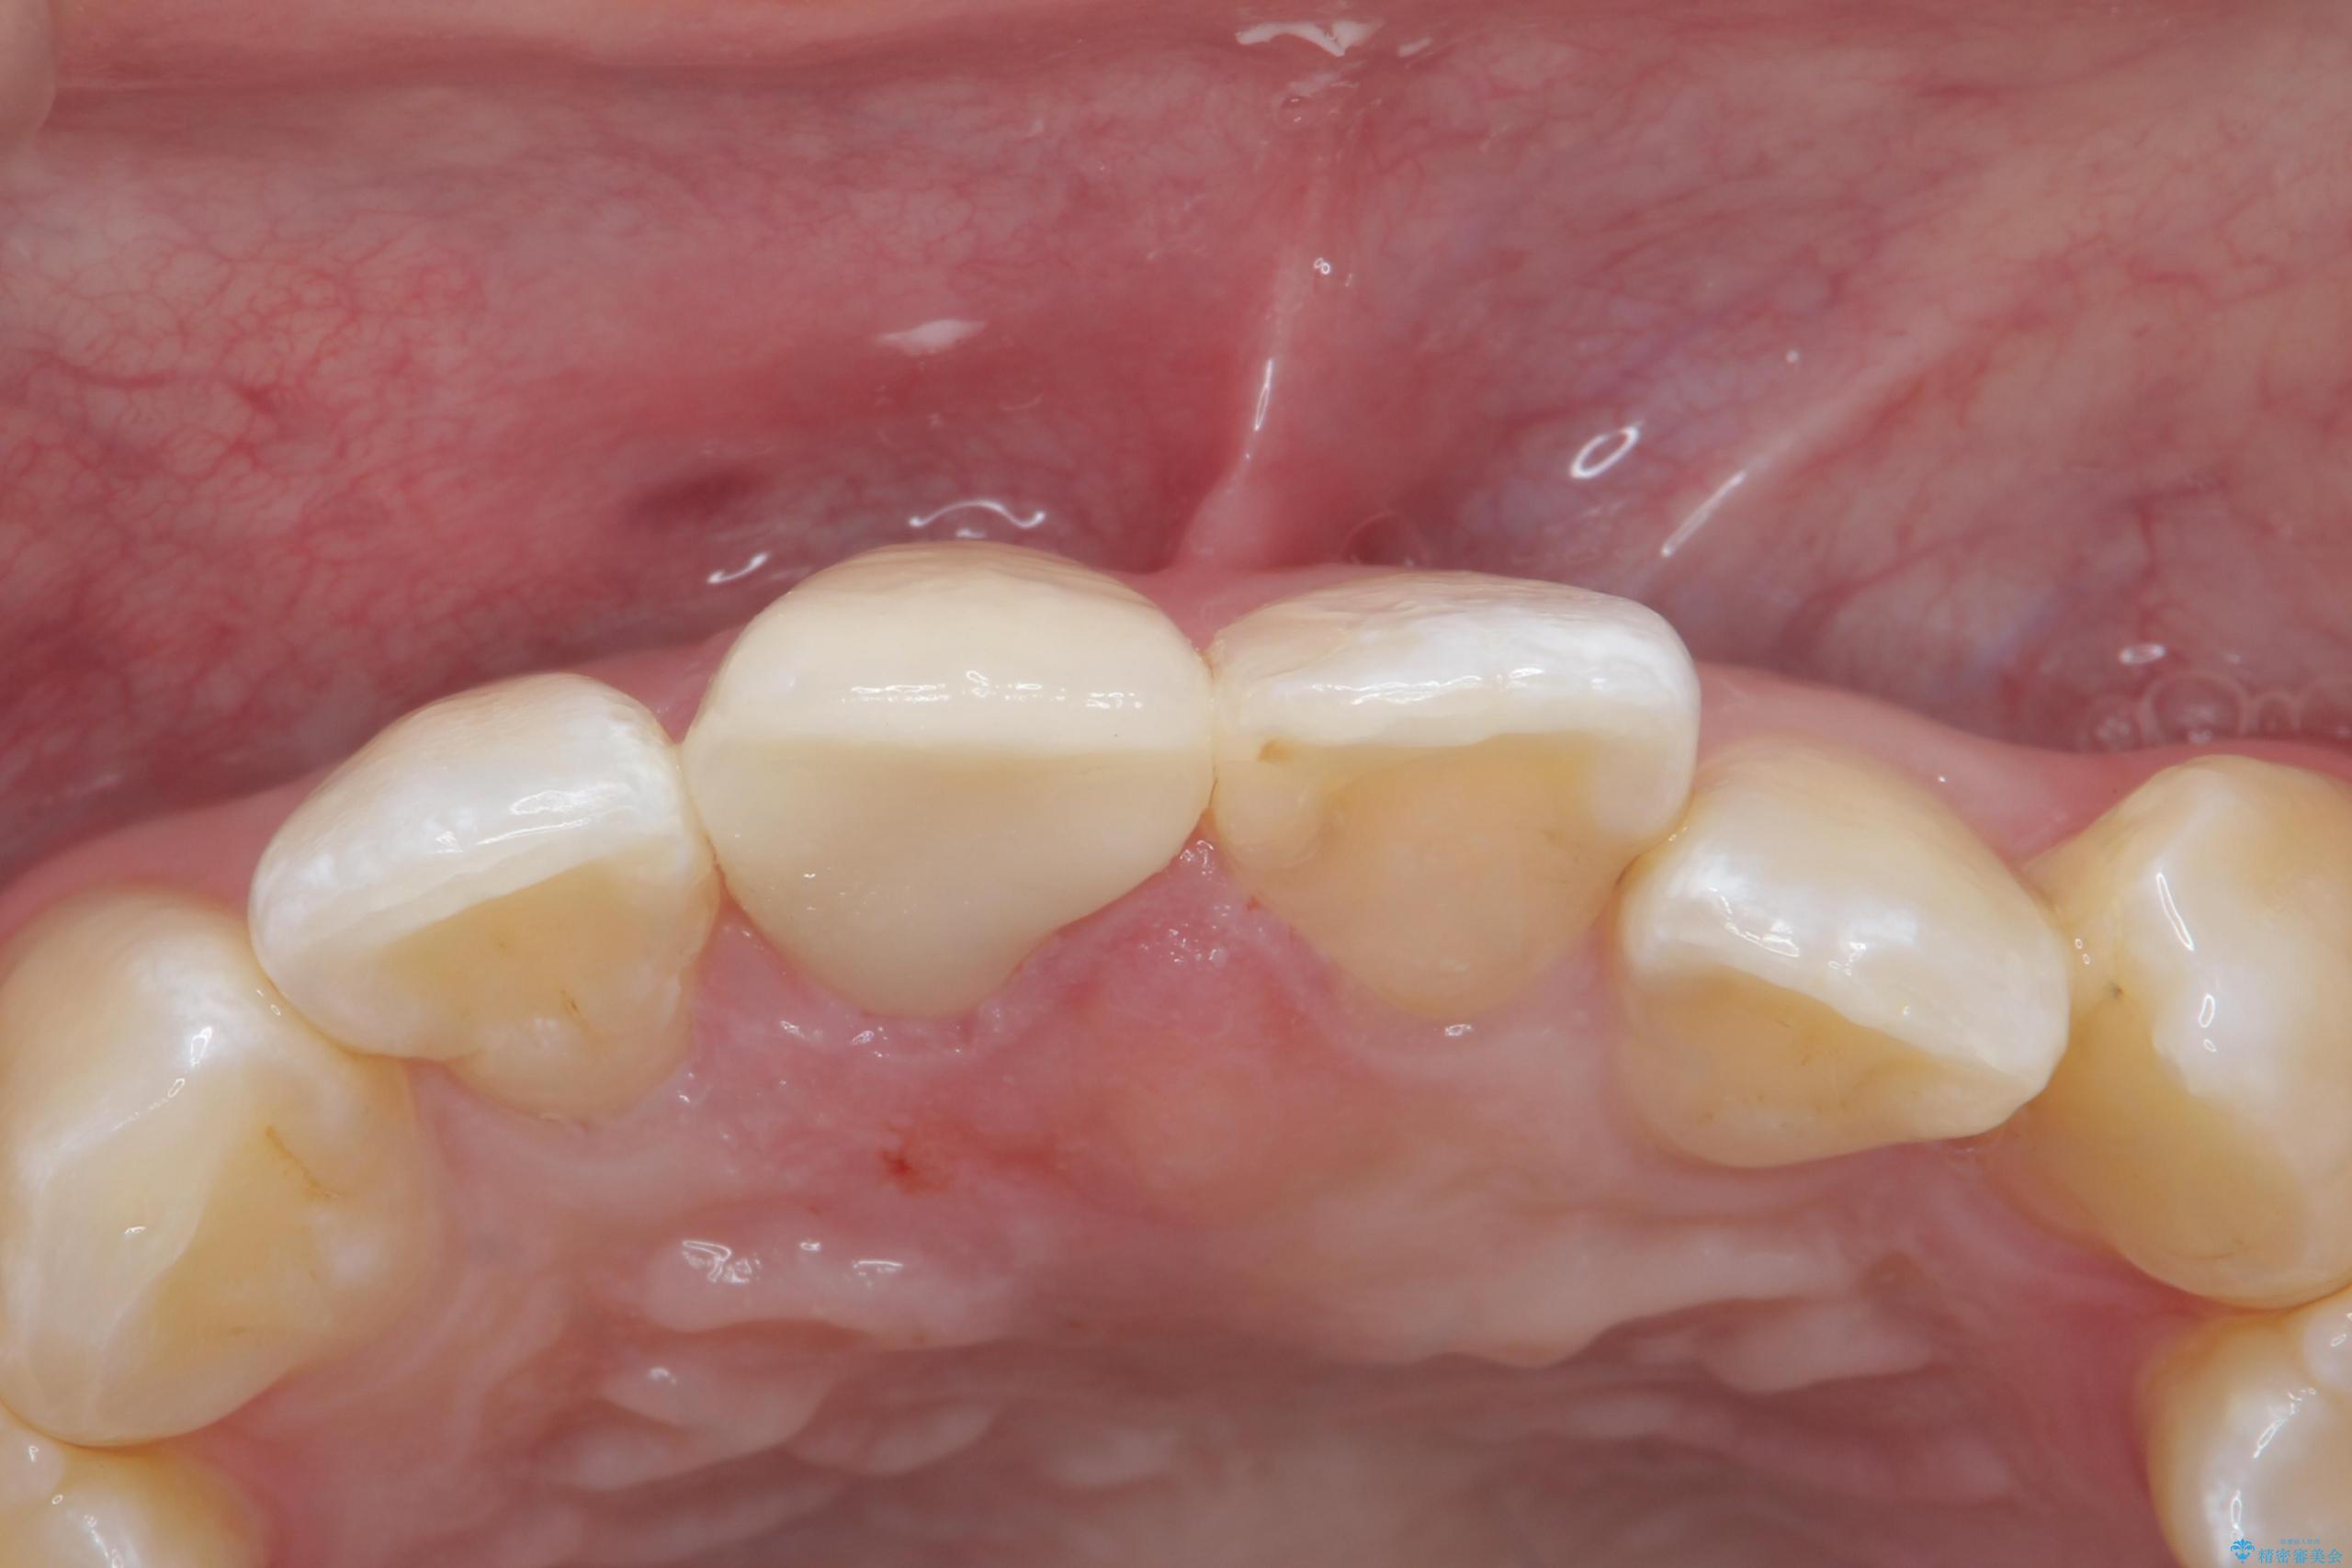

色・形ともに改善され、大変喜んでいただけました。